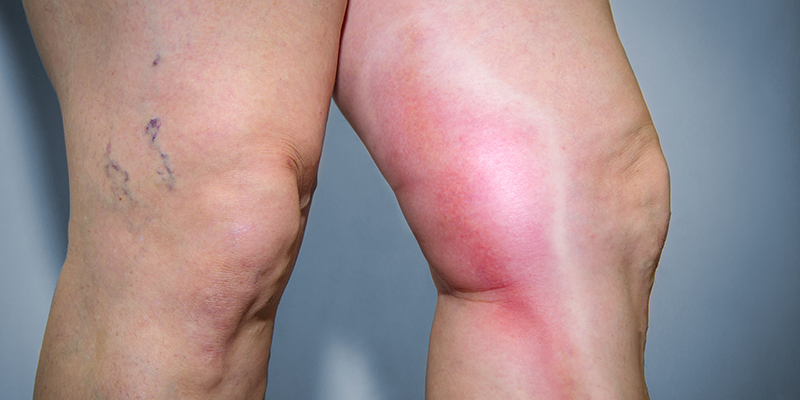

Longembolie, de meest gevreesde complicatie van diep veneuze trombose (DVT) is thans een van de belangrijkste oorzaken van moedersterfte1 2 Dit artikel beoogt inzicht te geven in de huidige opvattingen over diagnostiek, behandeling en preventie van DVT in de zwangerschapEen diepveneuze trombose (DVT), ook bekend als trombosebeen, is een trombose die meestal ontstaat in de bloedvaten van de benen, maar soms kan deze ook in de armen optreden het syndroom van Pagetvon SchrötterZiekteverschijnselen zijn een slapend (gevoelloos) been, pijn, een zwelling of rood been Indien een bloedstolsel (trombus) uit een diepveneuze tromboseDat heet diep veneuze trombose (DVT) Trombosebeen en arm Trombose in de aders van de benen komt het meeste voor In de arm komt het minder vaak voor Behandeling trombose Goed behandelen van trombose is belangrijk Hiermee kun je longembolie voorkomen Ook zijn hiermee ernstige complicaties,